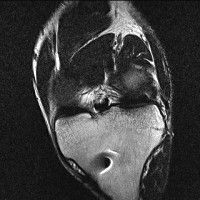

무릎 mri 간단히 봐주실 수 있으시나요 ㅠㅠ

안녕하세요 8년전 십자인대 수술하고 최근 무리한 운동에 무릎 불편감이 생겨서

mri 찍었습니다.

진단결과는 첫 찍은 병원에서 활액막염 이라는 진단을 받았습니다. 혹시 봐주실 수 있으실까요?

올라온 MRI가 단편적이라서 정확한 진단에 어려움이 있지만 십자인대에는 큰 이상이 있지는 않은것 같으며, 무릎관절내 물이 있는 것으로 보아 활액막염의 진단이 맞을 것 같습니다.

하지만 단편적인 영상이기 때문에 촬영병원에서 정확한 판독지 등을 받으시는 것이 좋겠습니다.